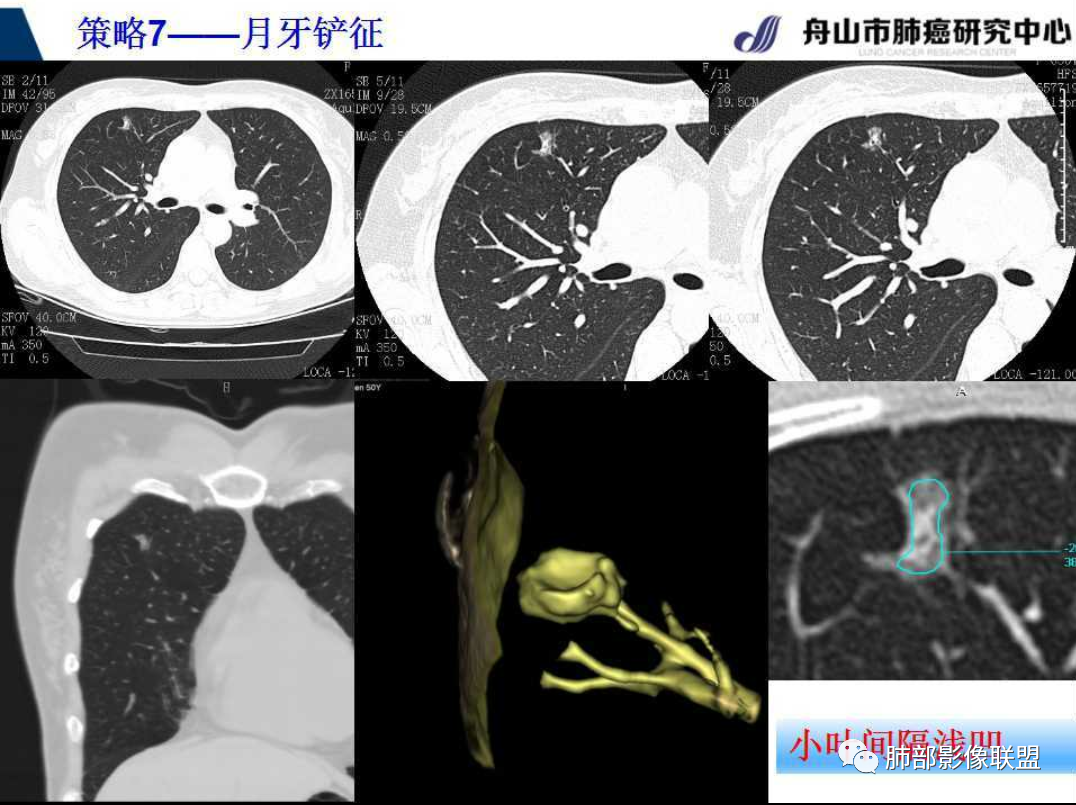

曹主任近期千聊的课件上就有“月牙铲”的解释及图片

2、影像所见:右肺上叶后段混合密度磨玻璃影mGGN,整体膨隆为主,局部收缩,局部边缘可疑月牙铲。周围磨玻璃影边界清楚,边缘分叶,细细观察这种清楚的弧形边界,与小叶间隔是否高度契合?!

结节内血管影增粗。病灶附近血管纠集,临近胸膜轻度增厚,叶间胸膜轻度牵拉移位。综合考虑恶性,腺癌可能。(局部胸膜增厚,考虑为肿块局部牵拉为主造成的)。